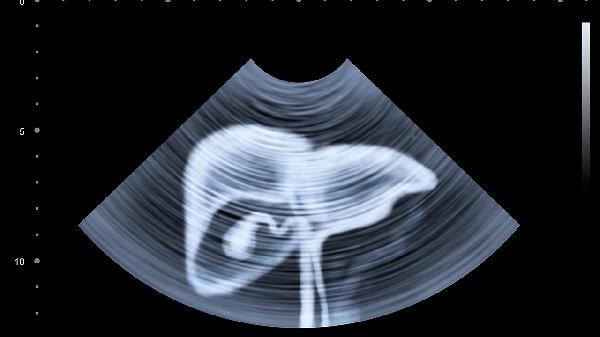

3、超声检查看变化

每年至少做一次肝脏超声,能直观看到肝脏形态。特别要注意门静脉宽度,超过1.3cm可能就是报.警信号。